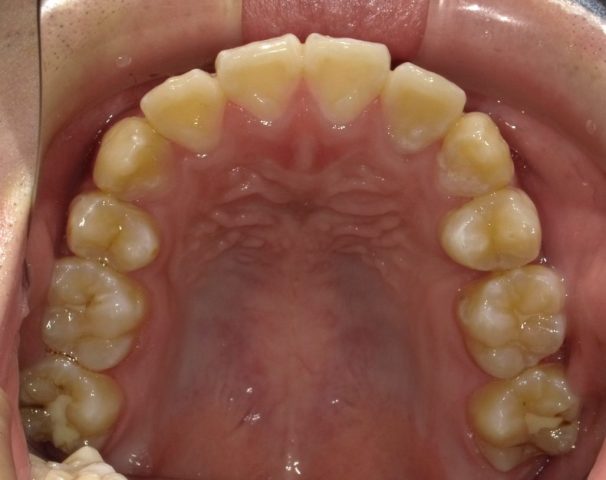

【上顎咬合面観】

2023年1月

| 治療方法・治療内容 | 4本抜歯・フルブラケット・ストレートワイヤーテクニック |